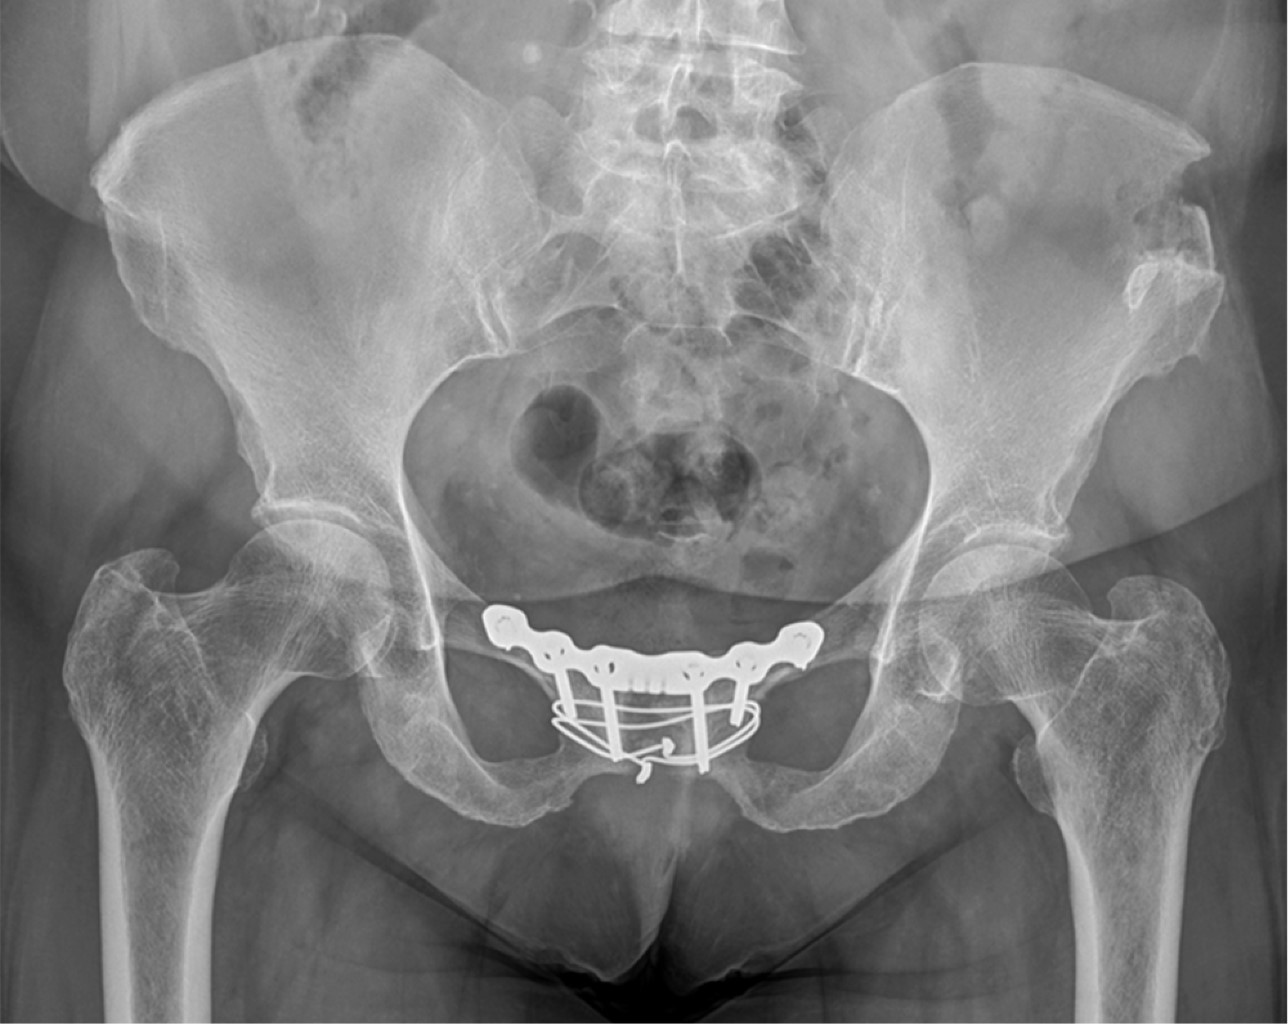

Con la paciente en decúbito supino se realizó una incisión de 12 cm discretamente convexa hacia distal a 3 cm encima de la sínfisis del pubis, tipo Pfannenstiel. Se incidió la fascia de Scarpa y Camper. El aspecto superior de la sínfisis púbica fue expuesto. Se realizó una disección separando y referenciando las inserciones del recto del abdomen desde la línea media para exponer un área suficiente a cada lado de la sínfisis púbica. De esta forma, se logró facilitar la inserción del injerto y la placa de compresión de cuatro orificios. En ambas pacientes se evidenció abundante tejido fibroso, en el lugar del cartílago se encontró tejido de granulación sobre la sínfisis, sugiriendo un proceso inflamatorio crónico y múltiples intentos de reparación. Se resecó el cartílago articular remanente de la sínfisis púbica y se continuó realizando un curetaje sobre la zona de del cuerpo púbico ya denudada sin cartílago (Figura 6). Al mismo tiempo, se realizó la toma de injerto mediante una incisión sobre la espina ilíaca. El tamaño exacto del injerto se determinó en función del tamaño del paciente y la superficie anterosuperior cureteada de la sínfisis. Se colocó el injerto óseo extraído sobre el defecto de la sínfisis y se fijó mediante un cerclaje de alambre (Figura 7). Se utilizó una paca de 3.5 Symphysis Locking Dynamic Compression Plate (SLDCP) (Synthes®, Malans, Switzerland).

Ambas pacientes fueron mantenidas en descarga durante cuatro semanas, con autorización para carga parcial a partir de la cuarta. Se sometieron a revisiones ambulatorias trisemanales, durante las cuales se observó una reducción escalonada de la analgesia y un aumento en la autonomía para las actividades diarias. En las revisiones, se realizaron radiografías en proyección anteroposterior y en carga (Figuras 8 y 9). A las 12 semanas, iniciaron ejercicios moderados sin impacto. El dolor significativo en la sínfisis del pubis, que inicialmente impedía la deambulación, se redujo gradualmente hasta su completa desaparición, con puntuaciones de 1 en la EVA. No se requirió la retirada del material de osteosíntesis en ninguna de las pacientes durante el seguimiento hasta el momento actual tras dos años de seguimiento.